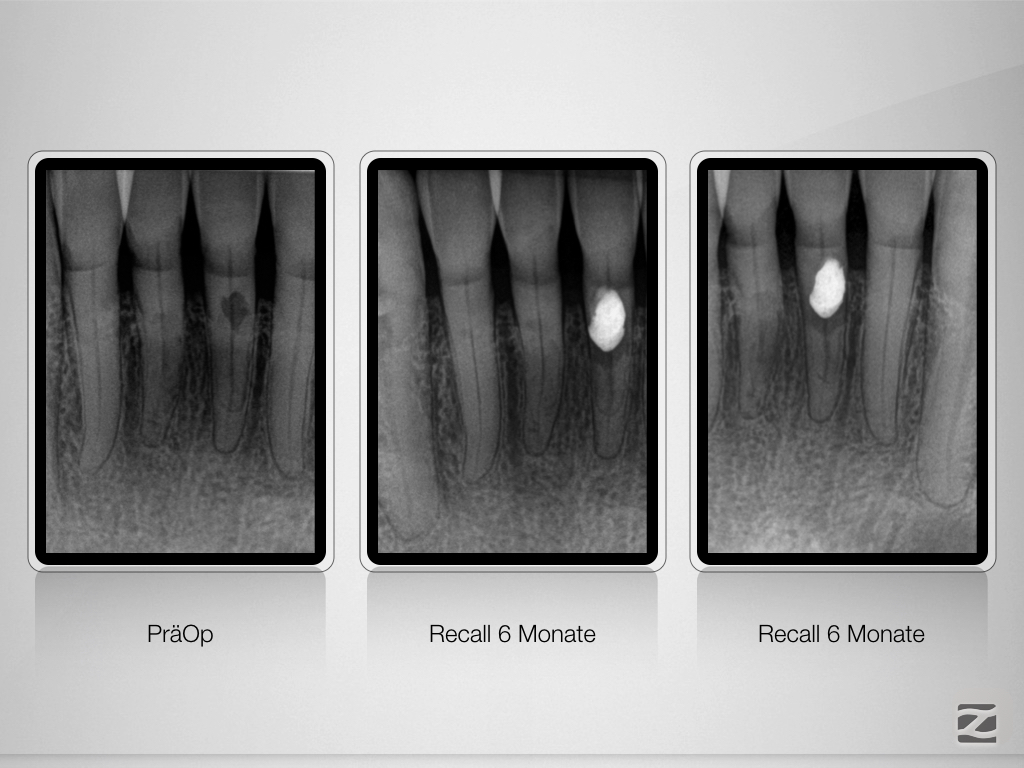

Trauma, externe Resorption & Pulpotomie